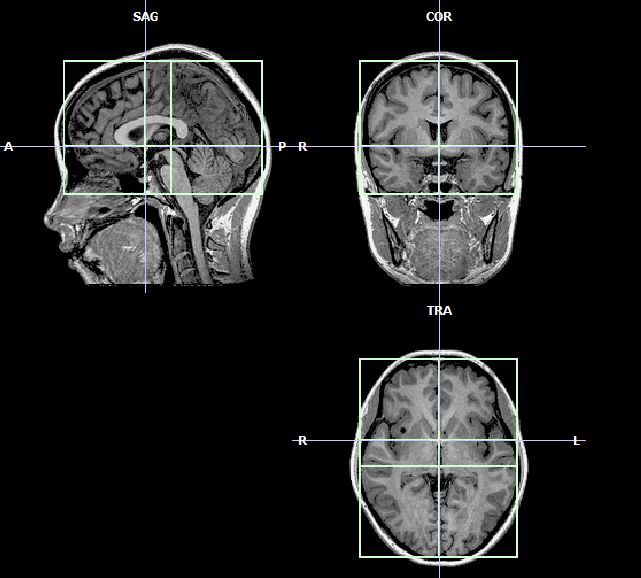

mriE’ in fase di attivazione all’Università di Nottingham un progetto di ricerca con risonanza magnetica (MRI) per scoprire se anormalità riscontrate nelle regioni frontali del cervello possono rendere maggiormente vulnerabili alla dipendenza da alcol, tabacco e droghe.

Finanziato su tre anni dal britannico Medical Research Council con 360.000 sterline, lo studio si concentrerà sulla corteccia frontale in quanto area del cervello alla base dei processi decisionali e della capacità di valutare i benefici a breve termine rispetto alle conseguenze negative a lungo termine di situazioni e comportamenti.